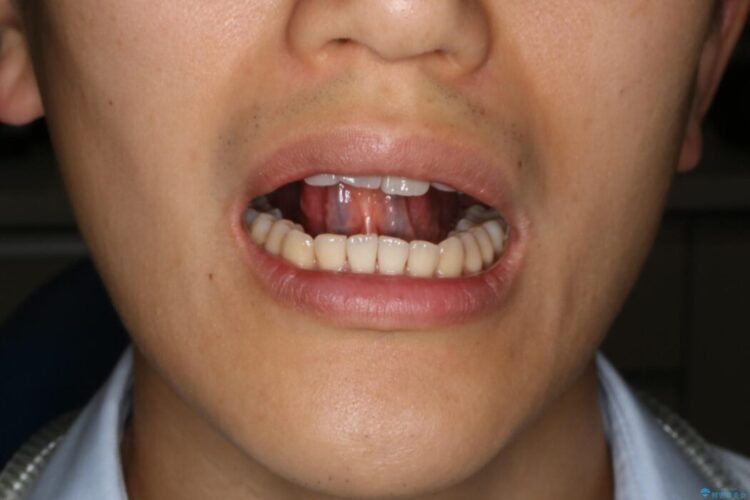

【20代男性】滑舌の悪さを改善したい!舌小帯切除術

滑舌の悪さを治したいとの主訴で来院、舌小帯切除術をご希望されました。

舌小帯は舌の下面についているヒダのことを指します。個人によっても違いますが、舌小帯が短い・硬い場合は舌の動きが制限されてしまいます。それによって滑舌の悪さ、摂食・嚥下に影響を及ぼすことがあります。